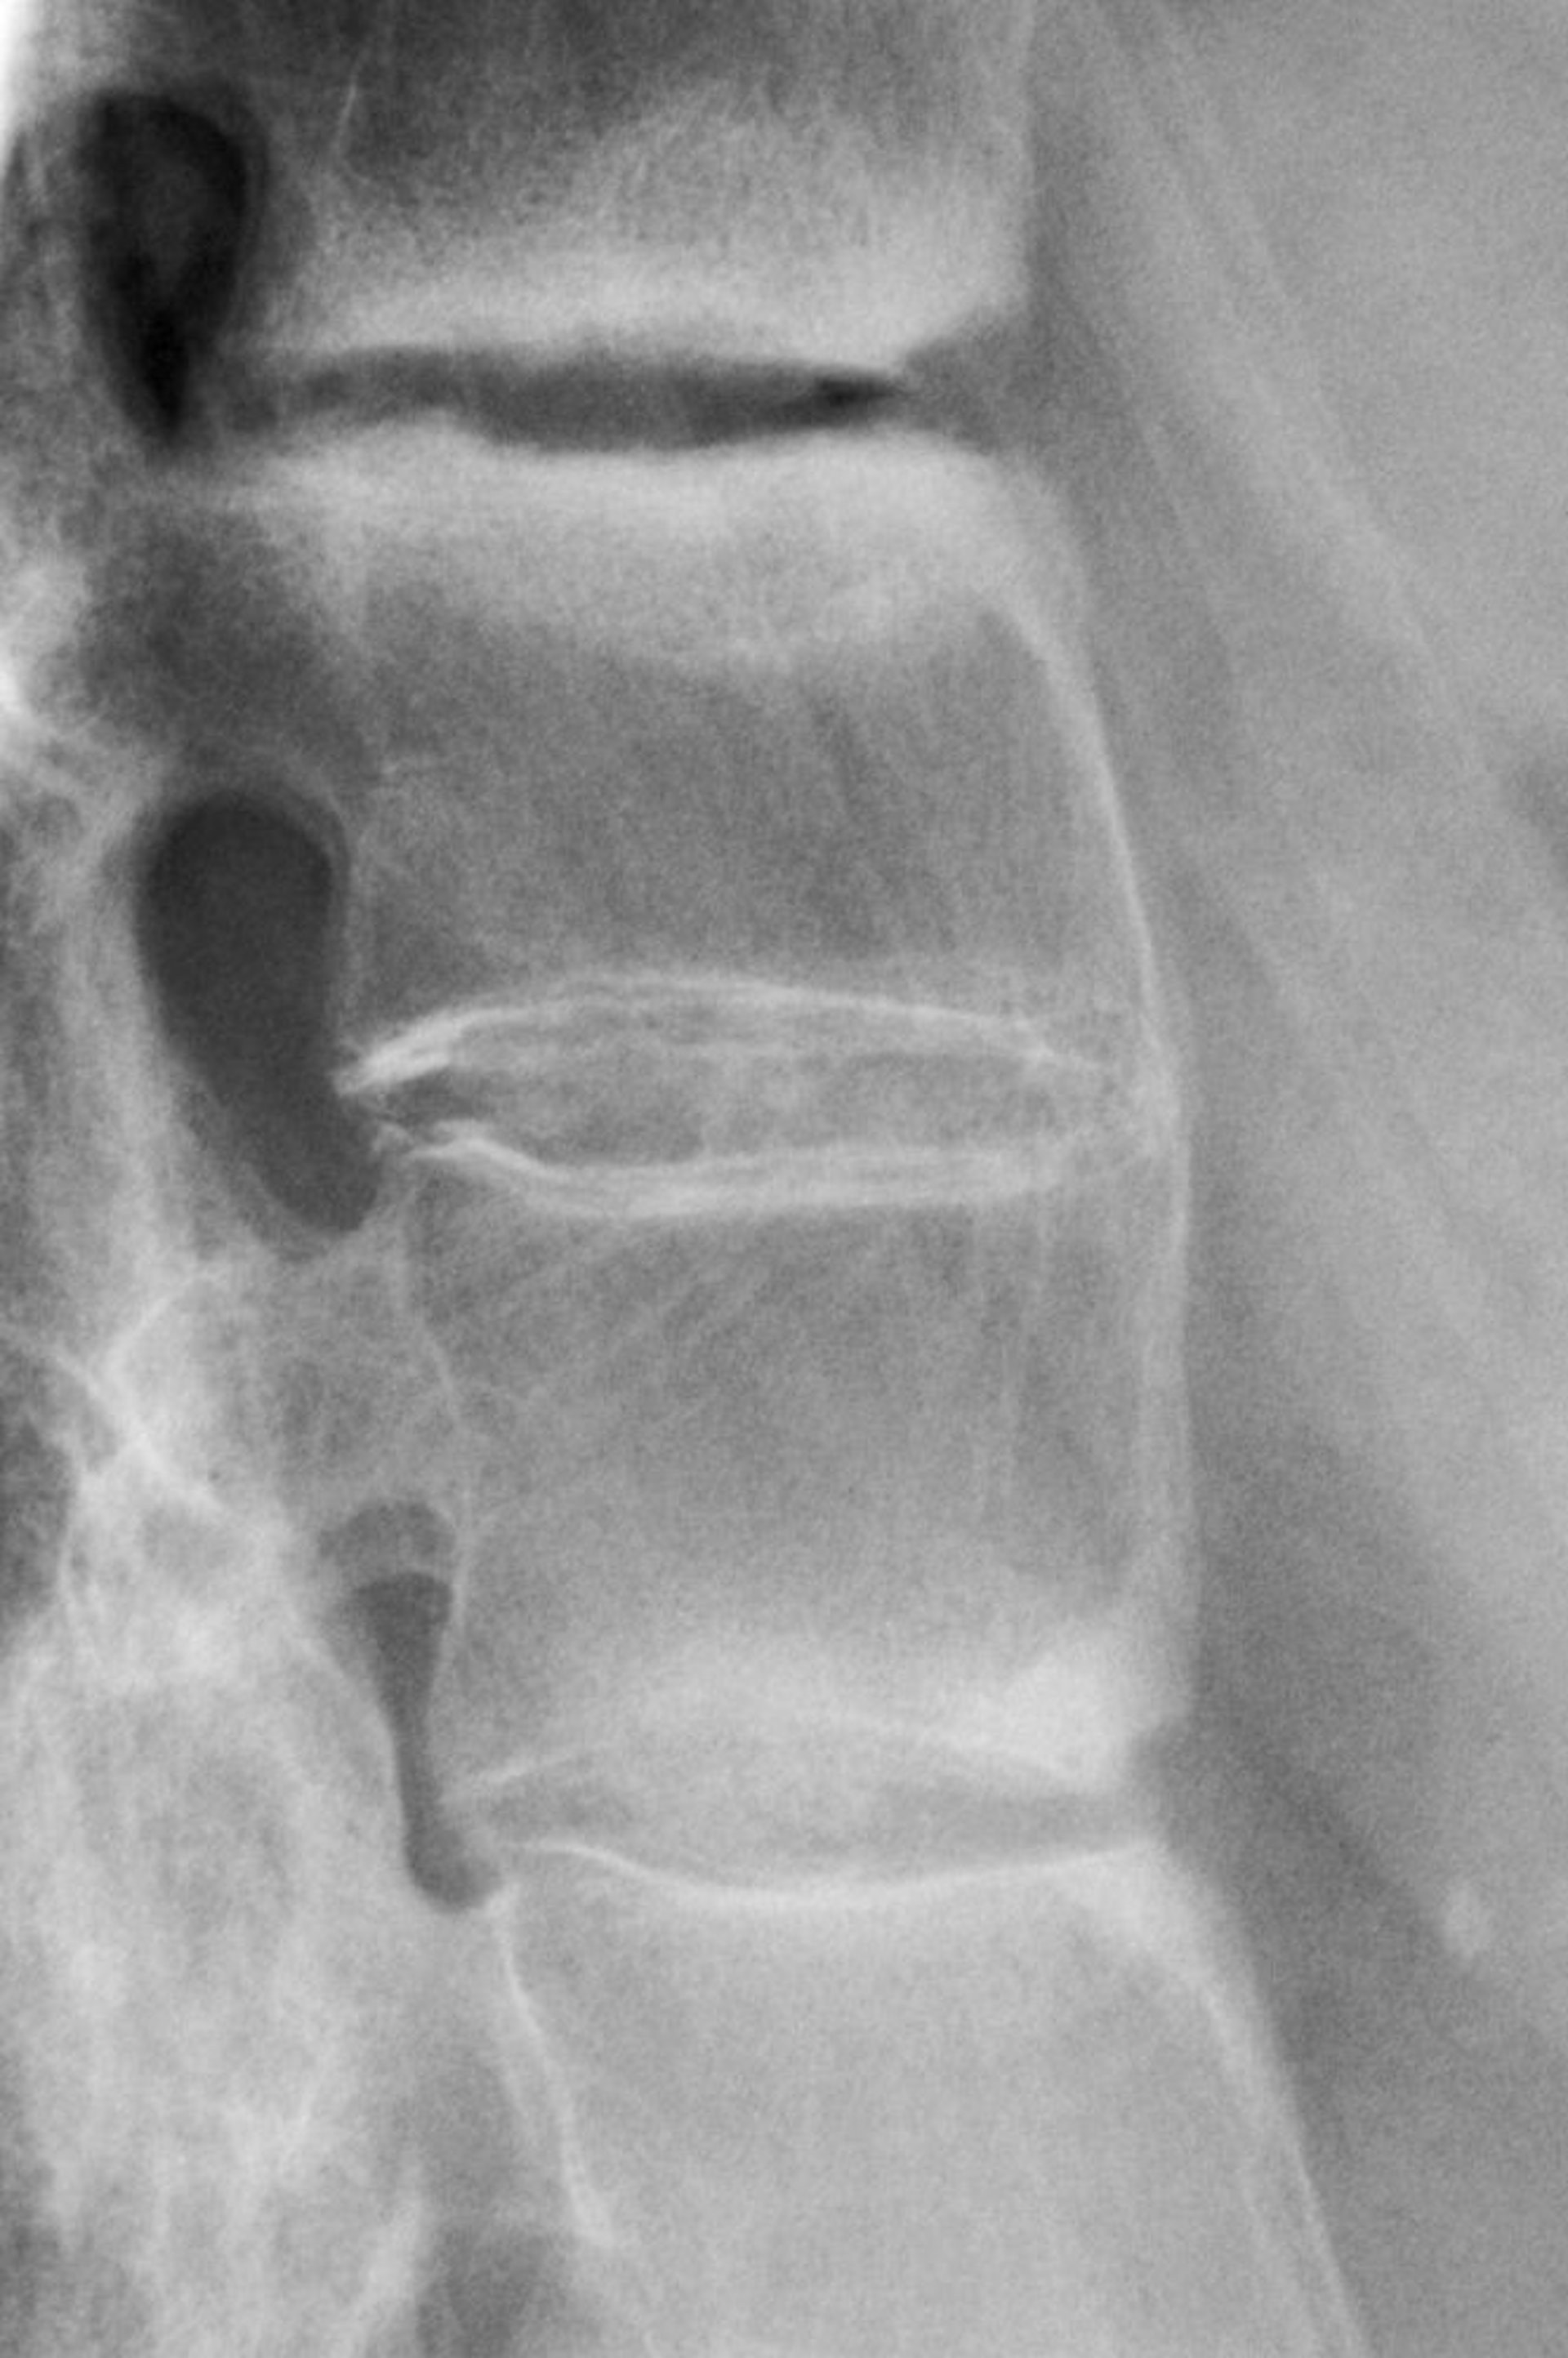

Espondilite anquilosante

Essa radiografia mostra esclerose entre as vértebras lombares, perda da lordose (fisiológica) e fusão das vértebras lombares, achado que indica espondilite anquilosante avançada.

DR P. MARAZZI/SCIENCE PHOTO LIBRARY